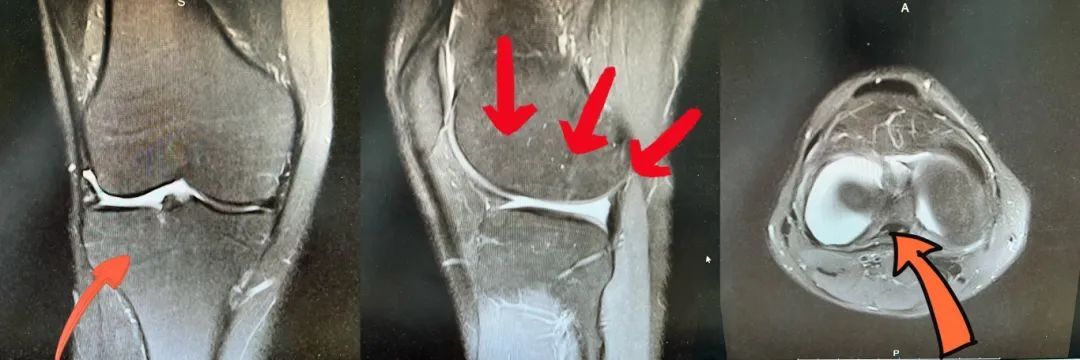

术前外侧半月板缺失,外侧间隙空虚

针对该患者病情,程飚团队采用MRI等影像技术对患者的膝关节进行详细评估,确认半月板的损伤程度和缺损区域。鉴于患者的年龄、活动水平及半月板损伤的严重性,决定进行半月板移植手术,以最大程度地还原关节结构和功能。完成一系列准备工作后,于近期为新疆小伙进行了关节镜下同种异体半月板移植术。手术非常成功,术后第二天患者即佩戴支具下地自主活动,并由科室康复团队开展术后康复锻炼。